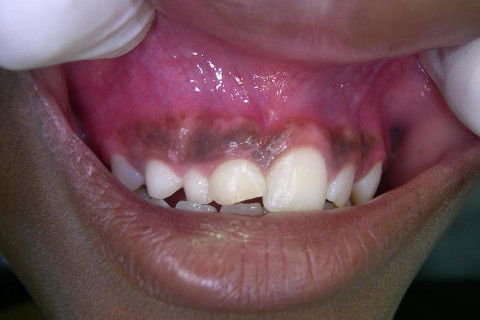

Visão do rebordo alveolar

No ambulatório de CTBMF do H.U. UNIUBE, recebo encaminhamento de jovem de 10 anos, gênero feminino, melanoderma e que vem encaminhada para avaliação de lesão cística em pré-maxila esquerda...

Exame clínico salienta a ausência dos dentes 11, 12 e 13 e ausência de necrose pulpar nos dentes envolvidos com a patologia que se apresenta.